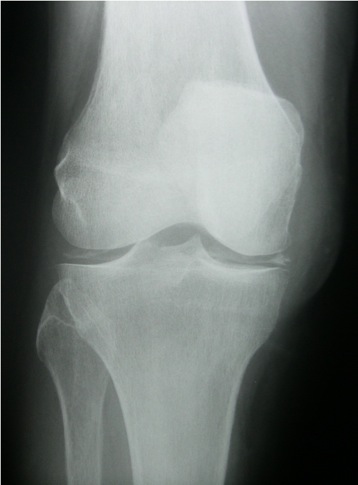

RIGHT KNEE:

Frontal and lateral views are submitted.  All osseous structures are in normal anatomic position.

Bone density is adequate.  Small osteophytes are noted at the distal femur and proximal tibia.  The medial tibiofemoral joint space is mildly reduced.  Calcification is noted within the tibiofemoral joint space, parallel to the subchondral bone.  There is a well-defined ossification in the soft tissues, posterior to the femoral condyles.

IMPRESSIONS:

1.	Calcium pyrophosphate deposition disease.

2.	Mild degenerative joint disease.

3.	Fabella.